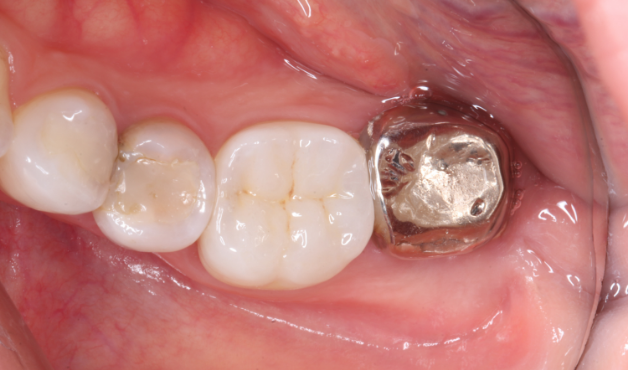

Before

主訴

歯を抜いた後インプラントが必要と言われた。

治療内容

自家歯牙移植 / イニシャルトリートメント(大臼歯)レジンコア / ジルコニアクラウン / 概形成・TEK作成 / 精密形成・TEKリマージン

治療期間

3ヶ月

治療費用

462,000

治療の

リスク

術後しばらくしてから骨性癒着、外部吸収を起こす可能性があります。